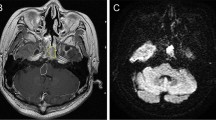

Chordoma present as osteolytic, destructive lesions with associated cortical destruction and soft tissue extension. Chordoma of the skull base are generally located in the upper half of the clivus and often extends to the lower half of the clivus, posterior clinoid process, cavernous sinus and occipital condyle [37]. Sometimes chordoma may also arise at the craniovertebral junction and involve the atlas and axis (see Fig. 1). The bulk of the tumour is usually located in the midline of the patient. [38] Extraosseous extension of the tumour can occur in all directions, from the nasal cavity to indenting of the pons, also called thumb-sign [39]. Chordoma are slow-growing lesions [1]. Although case reports have described intradural location, chordoma are usually extradural lesions [40, 41].

Chordoma. Imaging of a chordoma at the craniocervical junction. Computed tomography (a) shows lysis of the lower clivus. Axial T2-weighted imaging (b) shows a heterogenous, mostly hyperintense mass at the midline of the lower clivus. There is anterior extension to the oropharynx. The mass is hypointense on T1-weighted imaging (c) with heterogenous contrast enhancement (d). Pathologic examination confirmed the diagnosis of chordoma

On non-contrast CT, chordoma typically appear as well-circumscribed, hypoattenuating, heterogeneous lesion with extensive lytic bone destruction [42, 43]. The bulk of the tumour is usually hyperattenuating relative to the adjacent neuronal axis [44]. It may be difficult to distinguish between intratumoral calcifications, which are characteristic of the chondroid variant of chordoma [14], and sequestered fragments of the destroyed clival bone. There may be some separated areas of low attenuation within the tumour, probably also related to mucinous content [45].

The MRI characteristics of chordoma with the standard MRI sequences have been well described as early as the late 1980s and early 1990s [46,47,48,49,50]. Since then, MRI has come a long way. New developments in acquisition techniques, MRI detectors and the use of higher magnetic fields are pushing MRI resolution to almost histological levels. Chordoma can have variable signal intensity on T1, classically generally low-to-intermediate signal intensity, with sometimes small foci of hyperintensity, correlated with mucus or haemorrhage [46]. Classic chordoma show high T2 signal intensity with heterogeneous hypointensity, which may also be associated with mucous, haemorrhage and also calcification. The presence of haemorrhagic foci or calcification can be confirmed with gradient echo images or susceptibility weighted imaging (SWI), showing susceptibility artefacts [46]. Low signal intensity septations may be seen, which may correlate with areas of necrosis or cartilage seen in histology. Poorly differentiated chordoma may show different imaging characteristics. Yeom et al. [51•] showed hypointensity on T2-weighted images in three poorly differentiated chordoma. However, there is a lack of studies in larger poorly differentiated chordoma cohorts. Chordoma typically show moderate to marked Gadolinium contrast enhancement with honeycomb appearance, with linear areas of non-enhancement [52]. This may also be explained with the areas of necrosis, connective tissue or cartilage in the tumour at histology. Fat suppression imaging with suppression of the fatty bone marrow of the clivus may be useful in the delineation of clival chordoma [44]. Figures 1 and 2 show typical imaging characteristics of chordoma. More advanced imaging techniques will be discussed later.

Chordoma. Magnetic resonance imaging of a skull base chordoma arising at the clivus with compression of the brain stem. Axial T1-weighted imaging (a) shows a mass with mostly hypointense signal, a hyperintense focus (arrow) and heterogeneous contrast uptake (b, e). Axial FLAIR (c) shows heterogenous tumour intensity. T2-weighted imaging (c, f) shows mostly hyperintense signal intensity with linear foci of hypointensity. Pathologic examination confirmed the diagnosis of chordoma